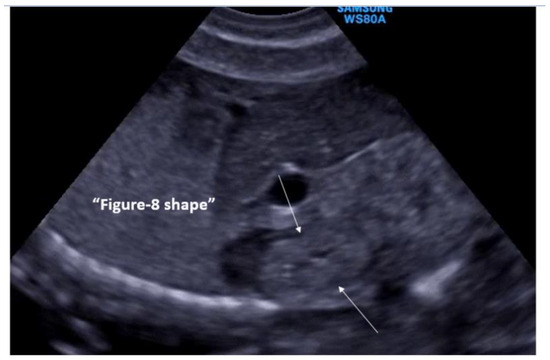

- Abuhamad, A.Z.; Horton, C.E.; Horton, S.H.; Evans, A.T. Renal duplication anomalies in the fetus: Clues for prenatal diagnosis. Ultrasound Obstet. Gynecol. 1996, 7, 174–177. [Google Scholar] [CrossRef]

- Jeffrey, R.B.; Laing, F.C.; Wing, V.W.; Hoddick, W. Sonography of the fetal duplex kidney. Radiology 1984, 153, 123–124. [Google Scholar] [CrossRef]